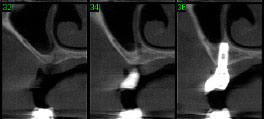

CASO 3 - Fratura de ATM

Paciente com história clínica de trauma. Fratura no côndilo direito com deslocamento do fragmento para medial e deslogamento do côndilo para lateral da cavidade articular.